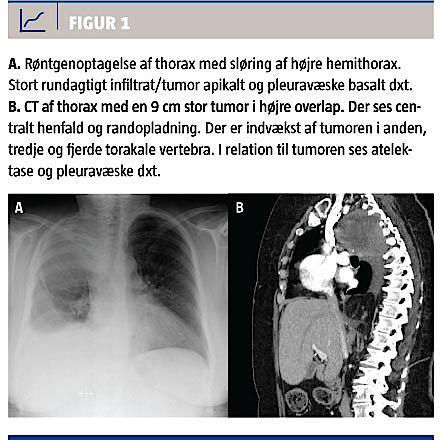

En 61-årig kvinde med psoriasis og epilepsi blev af egen læge henvist til røntgenundersøgelse af thorax, da hun havde tiltagende åndenød, og man ved stetoskopi fik mistanke om pneumoni. Der var ingen effekt af antibiotikabehandling. Røntgenundersøgelsen af thorax viste en central tumor med atelektase af højre overlap (Figur 1A). Ud over hoste klagede patienten over at have haft svedtendens og træthed gennem ca. en måned. Der var intet vægttab. Hun var aldrigryger og havde ikke været udsat for asbest eller partikelforurening. En spirometri viste en restriktiv lungefunk-tionsnedsættelse med en forceret udåndingsvolumen i første sekund (FEV1) på 1,1 l (45% af forventet), en forceret vitalkapacitet på 1,39 l (45,4% af forventet) og en FEV1/FVC-ratio på 79,37%. Patienten koopererede dog dårligt til undersøgelsen.

En CT med kontrast af thorax og øvre abdomen viste atelektase, en 9 cm rund proces posteriort i højre overlap samt højresidig pleuravæske og destruktion af corpus på anden, tredje og fjerde tora-kale vertebra (Th2, Th3 og Th4) (Figur 1B).